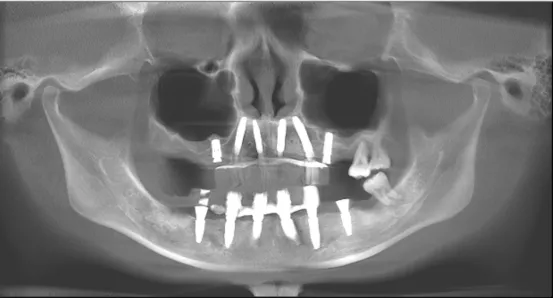

· 术后CBCT检查可见种植体植入位置佳,与术前设计一致。

· 修复体戴入后髁突位于关节窝内的适中位置。

· 植入精度分析,误差较小。

· X线片显示,种植体周骨稳定性、关节髁突位置评估均无异常。